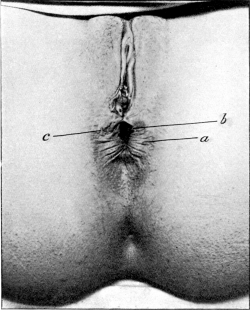

| 30. | Complete Laceration of the Perineum | 127 |

| 32. | Complete Laceration of the Perineum | 128 |

| 33. | Complete Laceration of the Perineum | 129 |